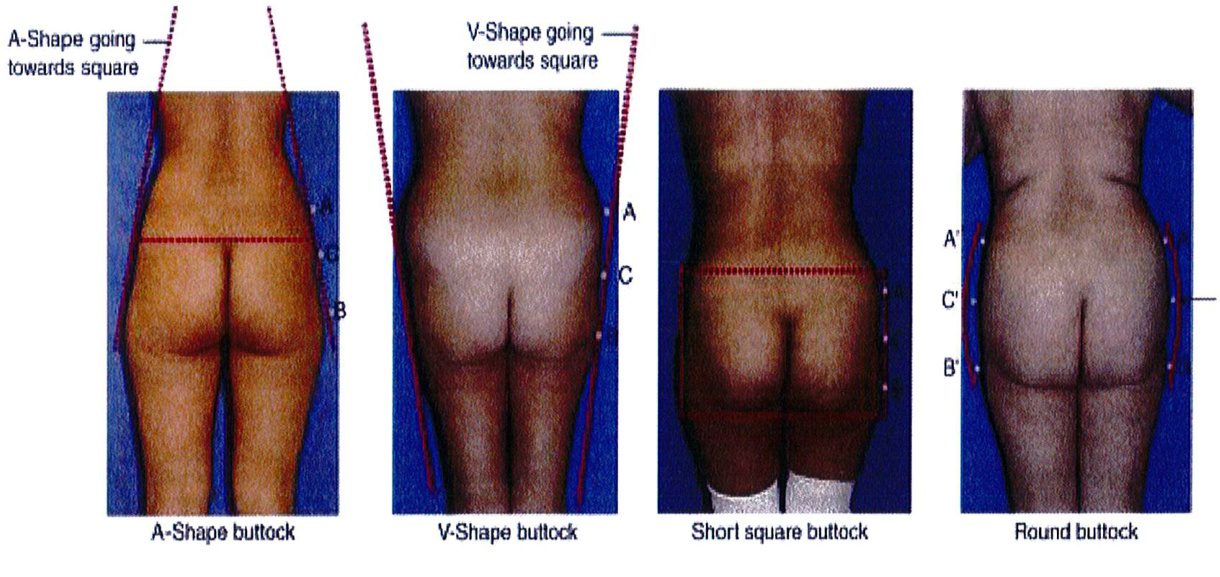

Sự kết nối các điểm A và B ở mỗi bên của cơ thế dẫn tới việc xác định 4 loại khung cơ bản: Hình chữ A, hình chữ V, hình vuông và hình tròn (Hình 5).

Điểm C có 2 chức năng: Đầu tiên là giúp phân biệt dạng mông tròn hay vuông. Mông tròn có lượng mỡ dư thừa ở điểm C này nhưng mông vuông thì có lượng mỡ bằng nhau hoặc lệch bên (Hình 5). Chức năng thứ hai và cũng là quan trọng nhất của điểm C là chúng giúp đánh giá mức độ lõm xuống ở điểm C trong mông vuông, mông hình chữ A hoặc hình chữ V. Mức độ lõm này được phân thành nhiều mức độ: 0, nhẹ, vừa, nặng (Hình 6).

Khung vuông là phổ biến nhất, gặp ở khoảng 40% số bệnh nhân. Vị trí A và B tương tự nhau, đặc trưng cho phần mông hình vuông để khi các điểm này nối với nhau sẽ được một hình vuông (Hình 7 và 8). Điểm C có thể có các mức độ lõm (thiếu mô mỡ) khác nhau. Đây là dạng khung dễ chỉnh hình nhất trong cả 4 kiểu khung vì bất kỳ sự thay đối nào ở 1 trong 3 điểm A,B,C đều có thể biến khung này thành dạng khung khác.

Dạng tròn gặp ở khoảng 15% số bệnh nhân. Dạng này có đặc điểm là xuất hiện lượng mỡ thừa ở điểm C. Khi cả 3 điểm (A, B và C) được kết nối với nhau, một đường cong hình chữ C sẽ được hình thành (Hình 10). Điểm C rất quan trọng vì nó giúp phân biệt khung tròn với khung vuông. Khi điểm C lõm dần, khung từ dạng tròn chuyển dạng vuông.

Khoảng 15% số bệnh nhân có dạng khung hình chữ V. Khi nối điểm A và B với nhau, có thể thấy chúng hội tụ lại 1 điểm ở dưới mông, tạo hình chữ V. Hầu hết mô mỡ nằm ở vùng mặt ngoài hông (điểm A) và rất ít ở điểm B. Ở dạng này, tình trạng lõm ở điểm C không quá đáng ngại. Khi điểm A nhỏ đi, mông sẽ có khung vuông.

Khung chữ A gặp ở khoảng 30% bệnh nhân. Khi nối các điểm A và B, tạo ra hình dạng gần như chữ A (Hình 11). Hình dạng này đặc biệt vì chúng tích nhiều mỡ ở hơn ở vùng đùi ngoài phía trên (điểm B) và ít chất béo hơn ở vùng hông bên (điểm A). Lý tưởng nhất là điểm A nhô ra nhiều hơn một chút. Lúc này, khi rút chất béo ở điểm B đi, mông bắt đầu có dạng vuông. Điểm C có thể bị lõm đi nhiều, song ở dạng này hầu hết các trường hợp chỉ lõm mức nhẹ hoặc trung bình.

Khung chữ A gặp ở khoảng 30% bệnh nhân. Khi nối các điểm A và B, tạo ra hình dạng gần như chữ A (Hình 11). Hình dạng này đặc biệt vì chúng tích nhiều mỡ ở hơn ở vùng đùi ngoài phía trên (điểm B) và ít chất béo hơn ở vùng hông bên (điểm A). Lý tưởng nhất là điểm A nhô ra nhiều hơn một chút. Lúc này, khi rút chất béo ở điểm B đi, mông bắt đầu có dạng vuông. Điểm C có thể bị lõm đi nhiều, song ở dạng này hầu hết các trường hợp chỉ lõm mức nhẹ hoặc trung bình. Dạng khung này thường được cải thiện khi hút mỡ ở điểm B hoặc vùng đùi bên (Hình 12). Điểm C có thể cần ghép mô mỡ, tùy thuộc vào mức độ lõm. Nên tránh hút mỡ quá nhiều ở điểm B để ngăn chặn điểm lõm ở khu vực này, ngẫu nhiên hình thành ranh giới giữa vùng mông và mặt ngoài đùi.